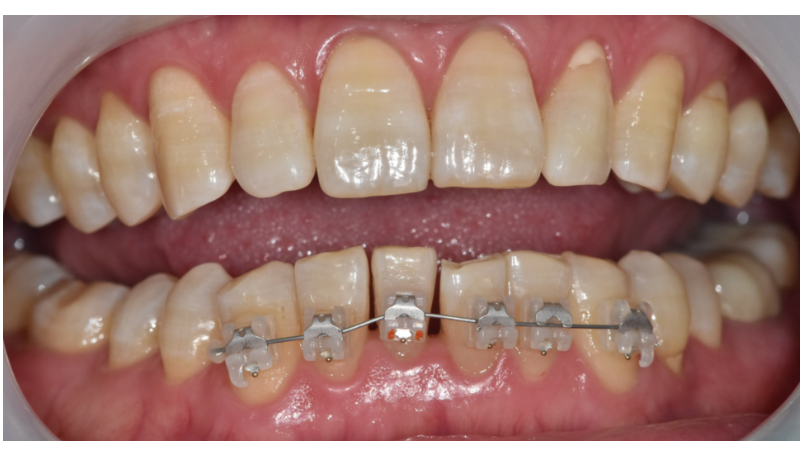

두번째, 장치의 종류

얼마전 자가결찰 브라켓에 대해

설명드린 적 있습니다.

자가결찰 브라켓은

마찰이 적어 치아이동이 빠른 편입니다.

예전 메탈 브라켓에 철사를 엮어

힘을 주는 방식은 힘 손실이 커서 속도가 느릴 수 있습니다.